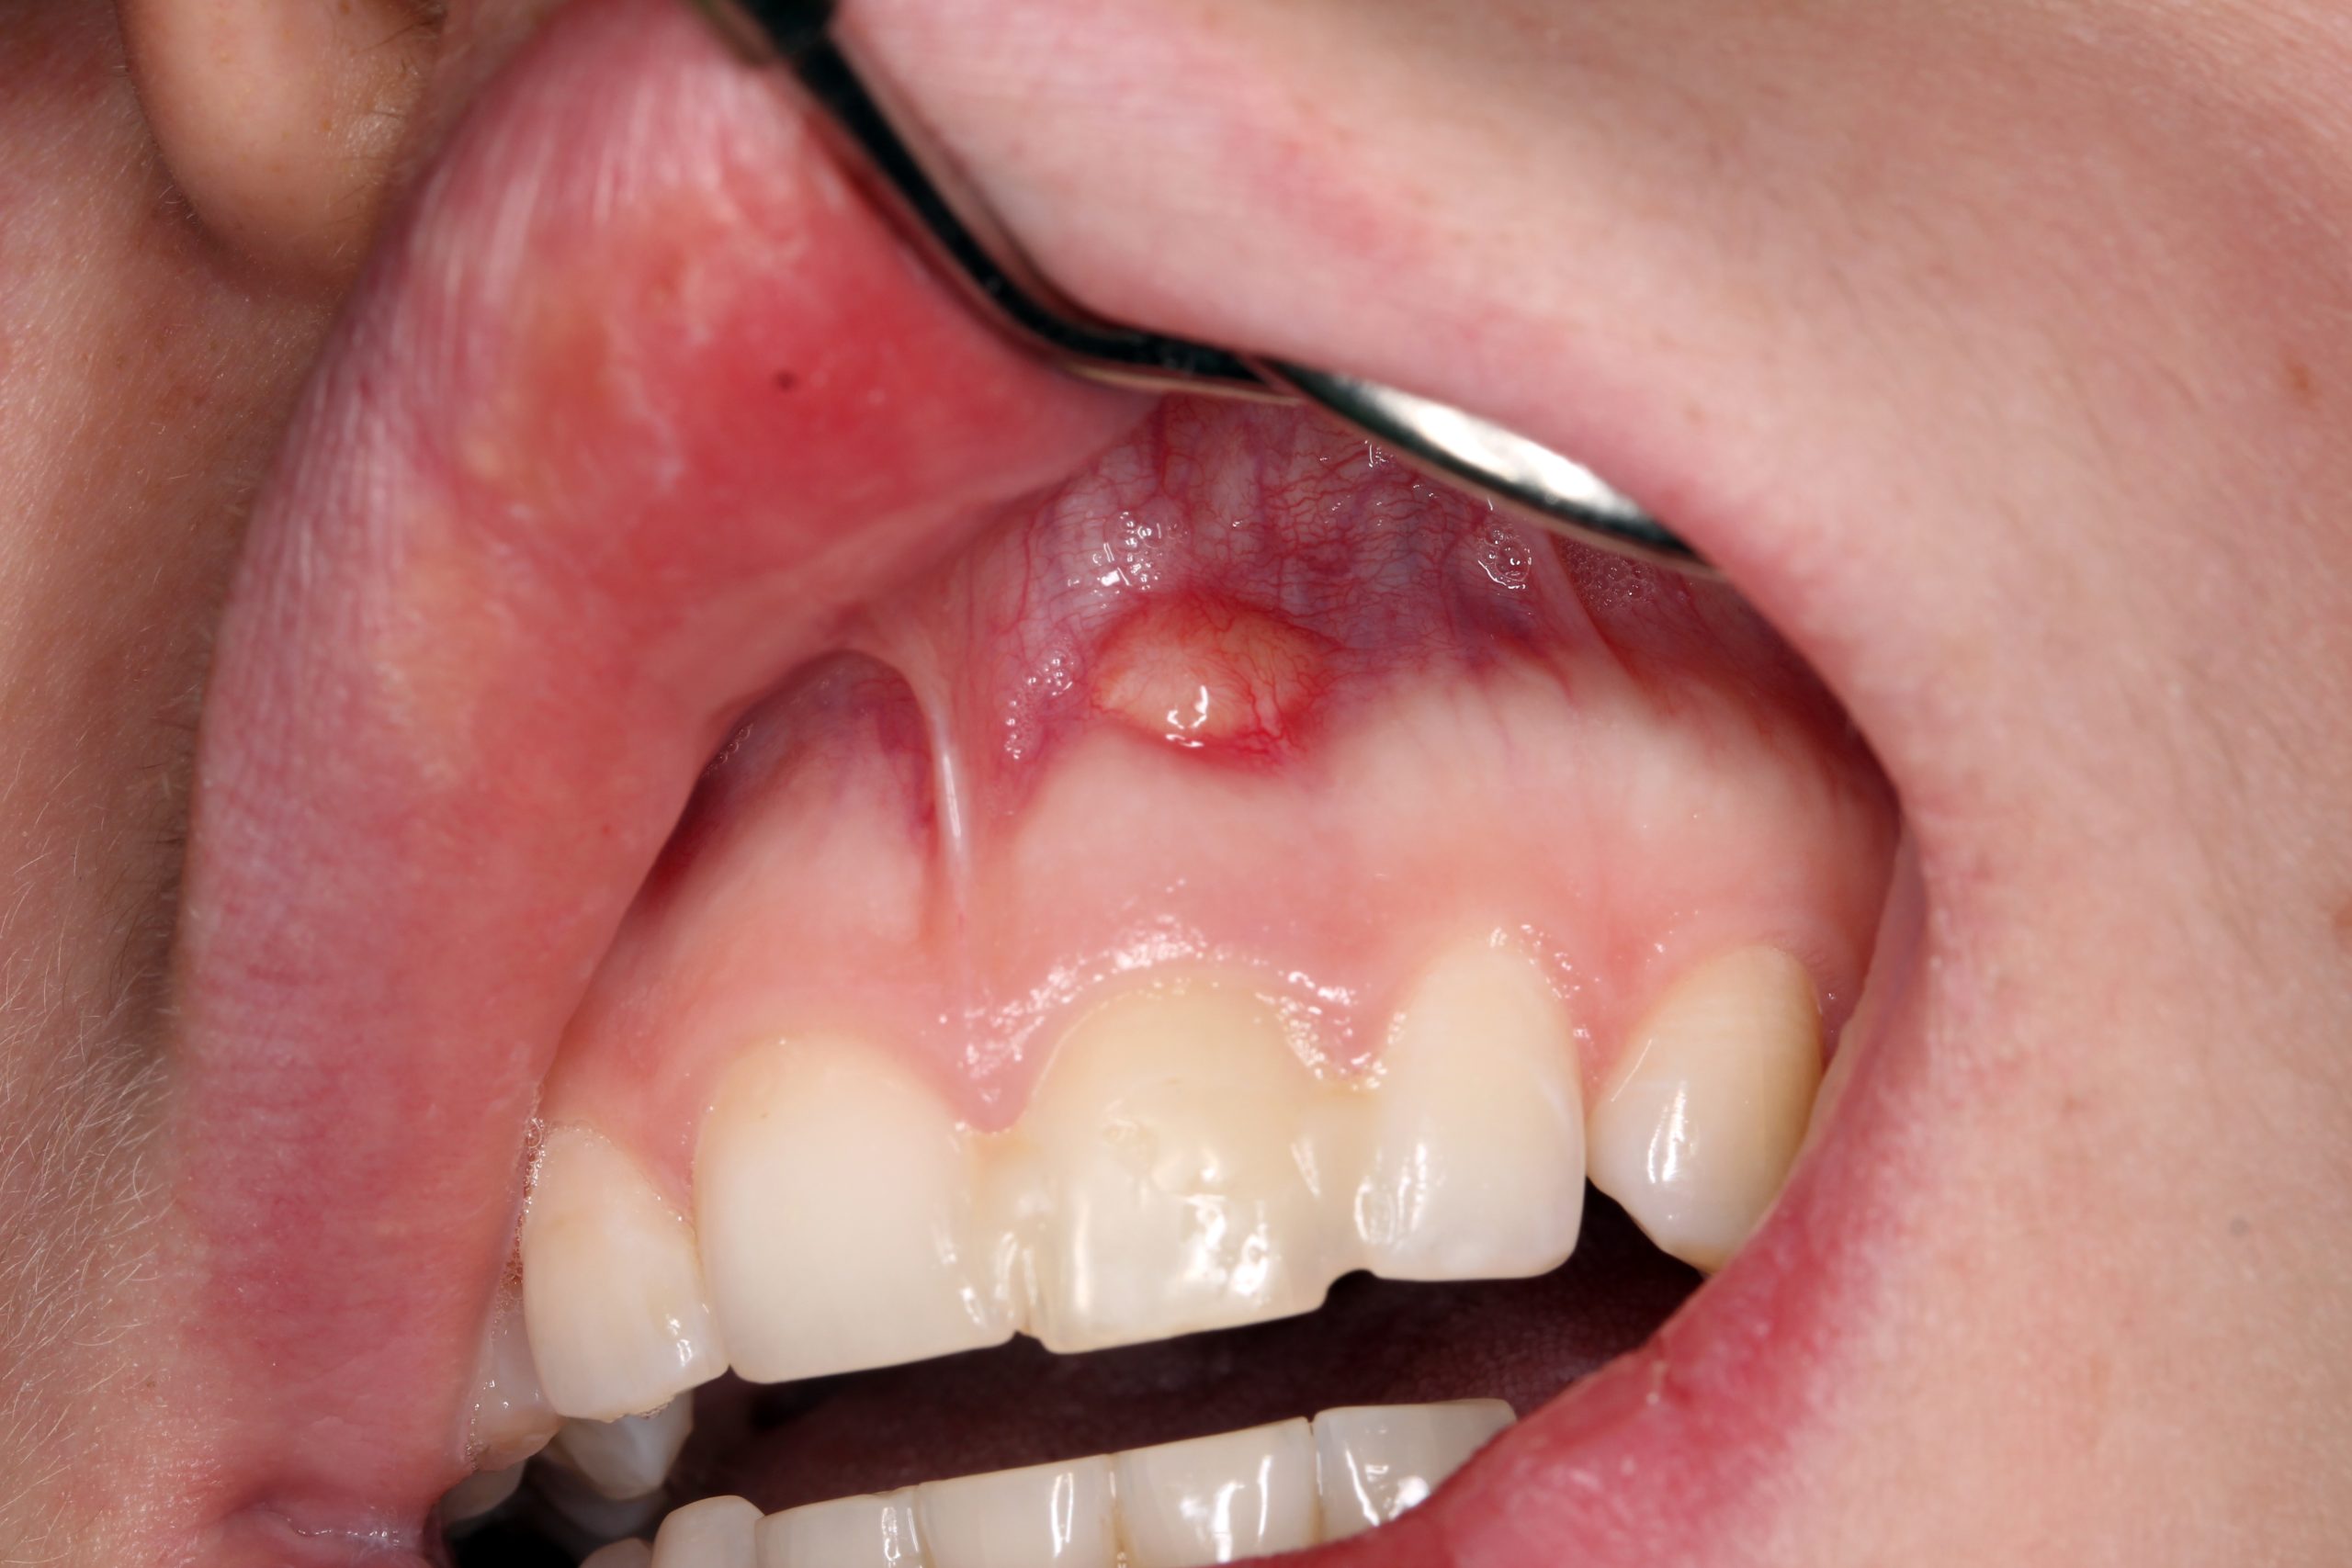

Initial situation: The irregularity of the smile line was caused by a deformation of the lip due to trauma.

A chronic fistula in region 21. The blocked tooth 21 with a different discoloration. The intraoral radiograph 21 confirmed incomplete endodontic treatment and partial root resorption.